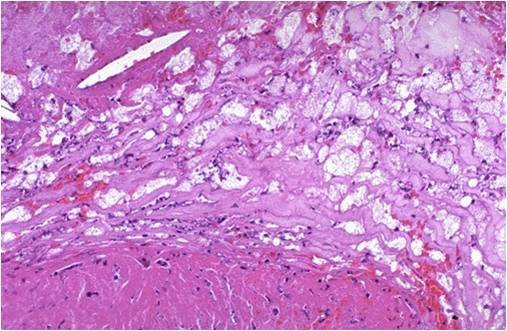

There is a severe degree of narrowing in this coronary artery. It is “complex” in that there is a large area of calcification on the lower right, which appears bluish on this H&E stain. Complex atheroma have calcification, thrombosis, or hemorrhage. Such calcification would make coronary angioplasty difficult.